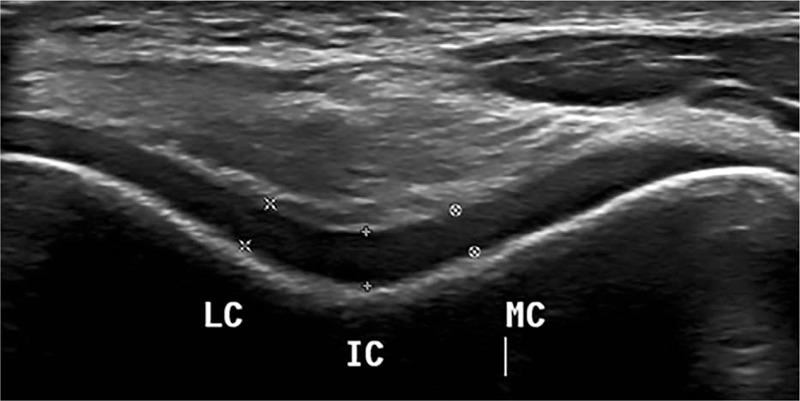

The aim of this study is to compare the distal femoral cartilage thickness of patients with type II diabetes mellitus with those of healthy subjects using ultrasonography. The study comprised 34 patients and 36 healthy subjects. Demographic characteristics of all the participants were recorded. The thickness of the femoral articular cartilage was measured using a 5-18MHzlinearprobe.Measurements were performed bilaterally from three points (intercondylar area, medial condyle, and lateral condyle). No significant difference could be found between patients and healthy subjects. Two demographic characteristics correlated positively with diabetic patients.

本研究的目的是使用超声检查比较II型糖尿病患者与健康受试者的股骨远端软骨厚度。该研究包括34例患者和36名健康受试者。记录了所有参与者的人口统计学特征。使用5-18MHz线性探头测量股骨关节软骨的厚度。从三个点(髁间区域、内侧髁和外侧髁)进行双侧测量。患者与健康受试者之间未发现显著差异。有两个人口统计学特征与糖尿病患者呈正相关。